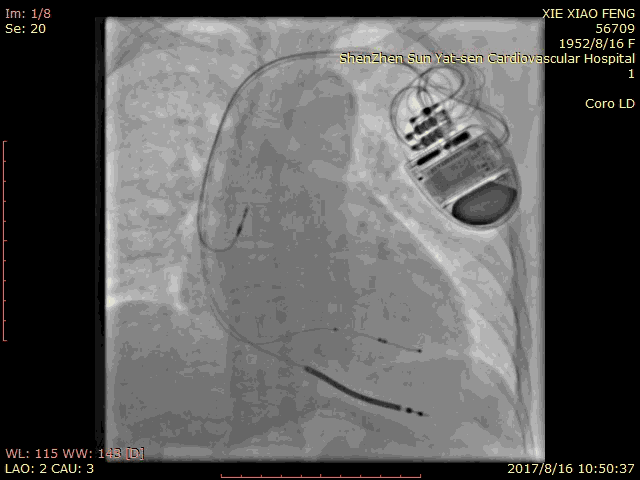

血管选择 一

血管选择二

血管选择三

术中测试

● 左心室阈值:LV4-Coil 1.25V

● 右心室阈值:0.5V

● 右心房阈值:0.5V

最终影像